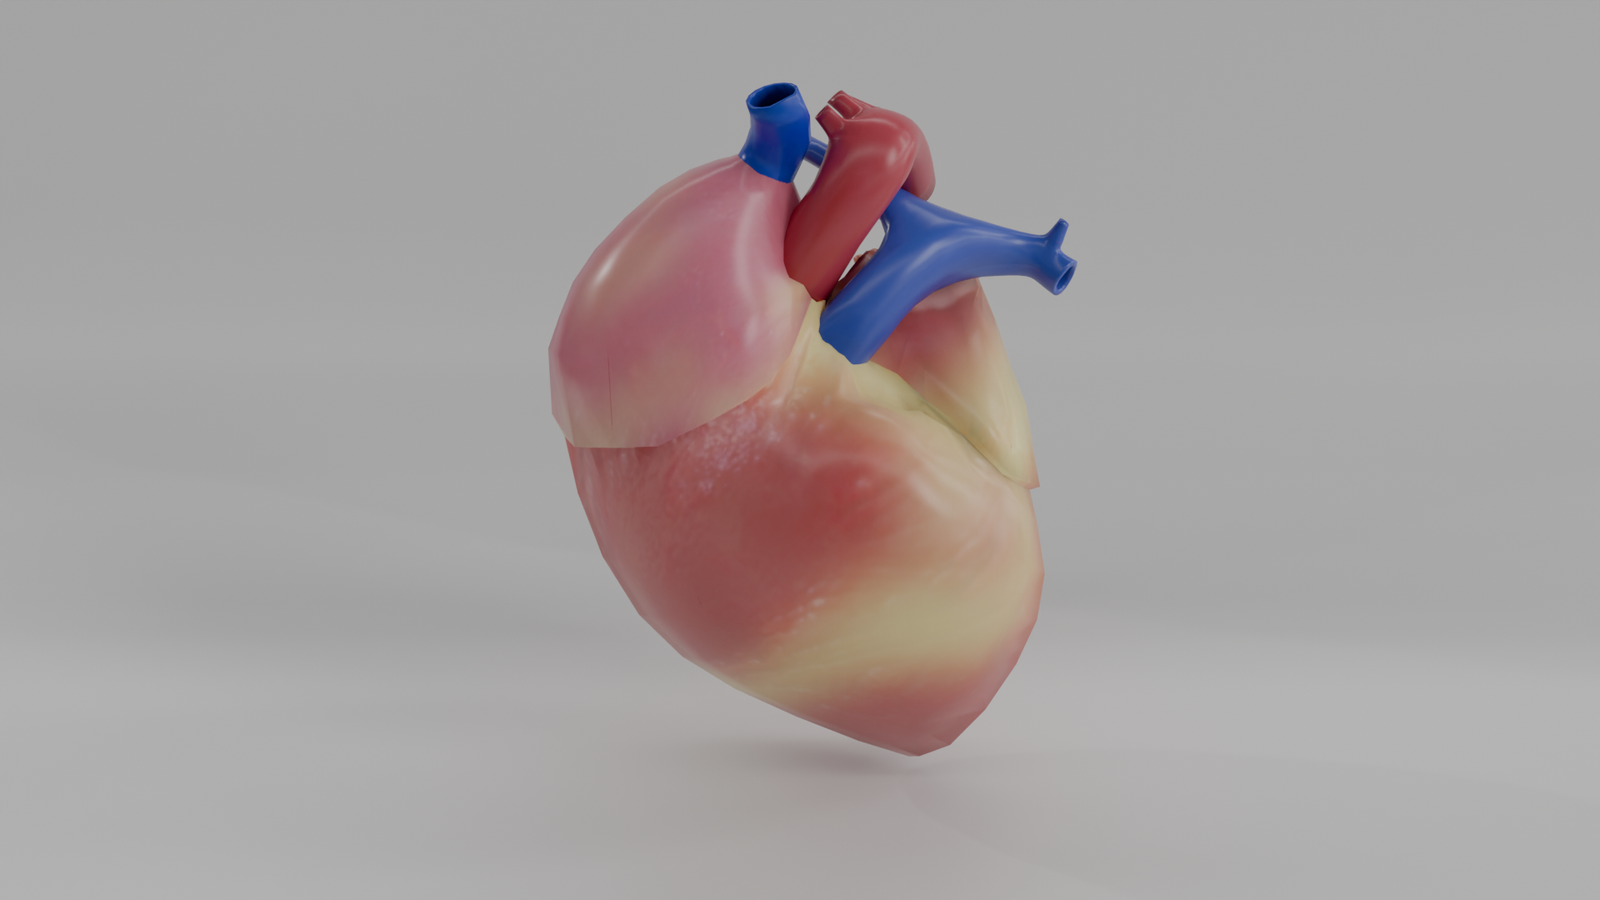

Corazón Humano

Modelo 3D educativo